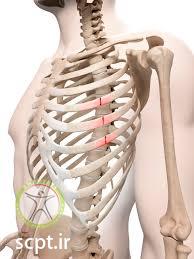

دنده ها از 12 جفت استخوان تشکیل شده اند که از جلو به استخوان جناق سینه و از قسمت پشت به ستون مهره ها متصل می باشند و در مجموع تشکیل قفسه سینه را می دهند. کار قفسه سینه این است که از ارگان های اصلی و حیاتی بدن همچون قلب و شش ها حفاظت کند.

10 درصد از بیمارانی که دچار ضرب دیدگی در قفسه سینه میشوند، دچار شکستگی دنده میشوند. شایع ترین منطقه شکستگی دنده بین دنده های 4 تا 10 میباشد و شکستگی دنده های اول و دوم به ندرت تفاق میفتد. ( فقط در تصادفات و سقوط از ارتفاع ایجاد میشود )